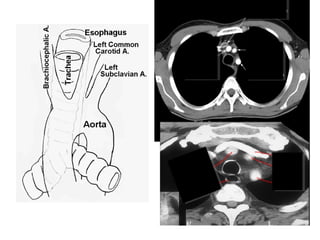

Mr HR, 65yo

Chest & Back Pain 4d before

admissions

Uncontroled hipertension,

DM

History (+) 6 month